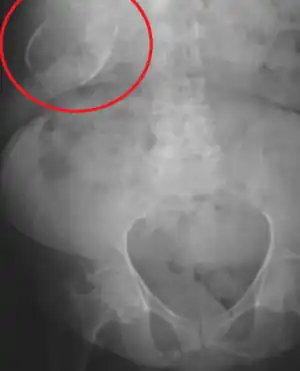

Vesícula biliar de porcelana

A vesícula biliar de porcelana é uma calcificação da vesícula biliar acreditada ser causada pelos cálculos biliares excessivos, embora a causa exata não esteja clara. Como na doença de cálculo biliar em geral, esta condição ocorre predominantemente em pacientes femininas de meia-idade com sobrepreso. É uma variante morfológica da colecistite crônica. A cicatrização inflamatória da parede, combinada à calcificação distrófica dentro da parede transforma a vesícula biliar em um vaso assemelhado à porcelana.

Radiografia abdominal (raio-X), ultrassom abdominal ou tomografia computadorizada.